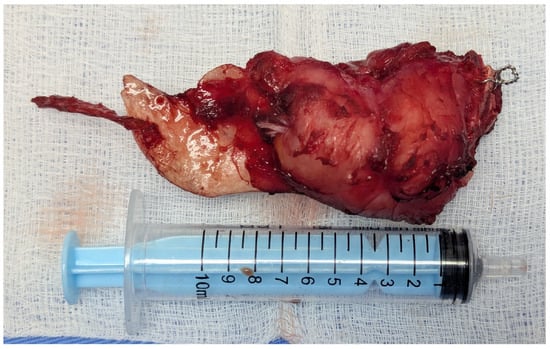

2.2. First Surgical Intervention

2.4. Second Surgical Intervention

2.5. Third Surgical Intervention